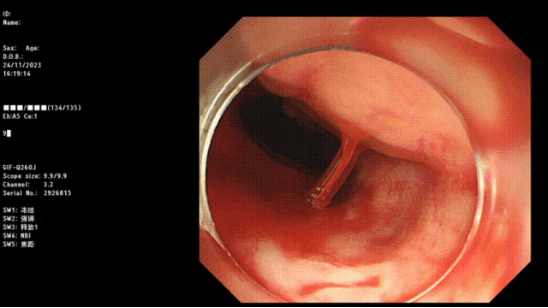

Part.04病因診斷有哪些方式?

1. 內(nèi)鏡檢查:包括胃鏡、結(jié)腸鏡等內(nèi)鏡檢查技術(shù),可以直接觀察到消化道黏膜的情況,幫助醫(yī)生確定出血的原因。

2. 影像學(xué)檢查:腸道CT、核磁共振等影像學(xué)檢查方法能夠提供更全面的圖像信息,有助于找出隱匿的病變。

3. 血管放射下造影可以找出出血部位。